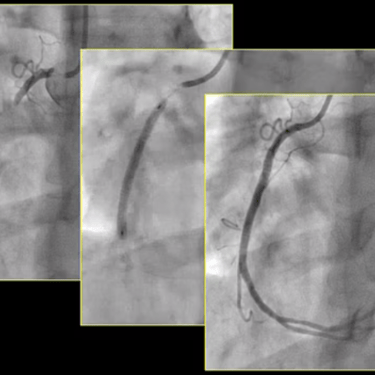

Invasive Angiography

Invasive coronary angiography is a procedure that uses contrast dye and X-rays to visualise the heart’s arteries, assessing for blockages. It is performed under local anaesthesia, typically via wrist access, to guide treatment decisions for coronary artery disease.